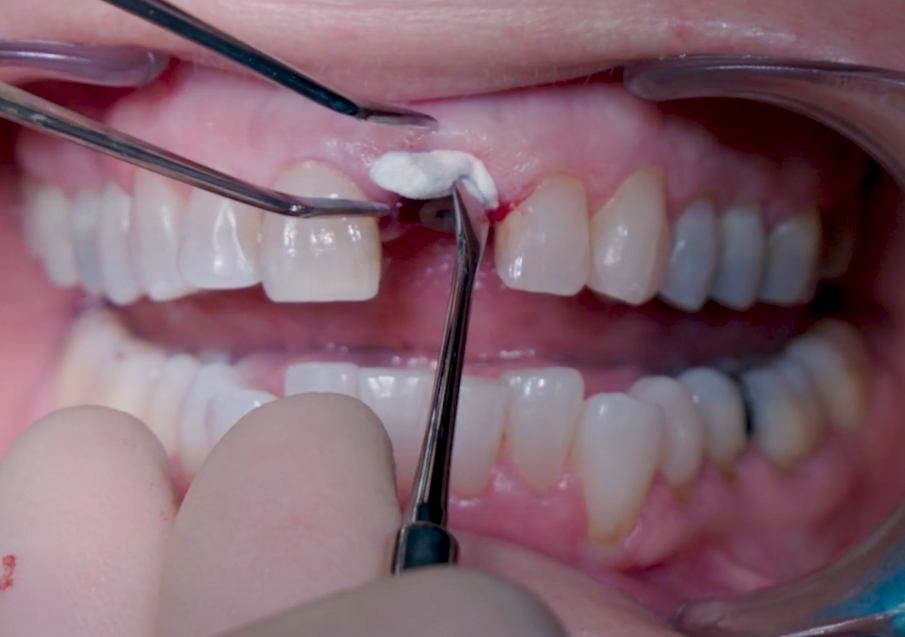

Dopo l’inserimento, la posizione dell’impianto è stata verificata orizzontalmente con uno specchio occlusale e verticalmente con una sonda chirurgica e a questo punto è stata selezionata l’altezza gengivale dell’abutment (Figg. 11, 12). Un abutment di guarigione è stato posizionato sull’impianto (Fig. 13) per proteggere la connessione in modo che l’osseo granulare sostitutivo (Straumann XenoFlex) potesse essere applicato nella fessura tra l’impianto e la parete vestibolare. Questo è stato delicatamente compattato con il lato di 2,8 mm della sonda chirurgica (Figg. 14–16). Il Collacone (biomateriali botiss) è stato utilizzato per tenere i granuli ossei lontano dai margini gengivali, allo scopo di evitare la fenestratura dei tessuti molli e l’infiltrazione fibroblastica (Figg. 17, 18).

Figg. 14, 15_XenoFlex Straumann applicato sulla cresta vestibolare.

Fig. 16_Condensazione dei granuli con sonda chirurgica.

Fig. 17_ Applicazione del collacone (botiss biomaterials).

Fig. 18_Applicazione biomateriale finalizzata.